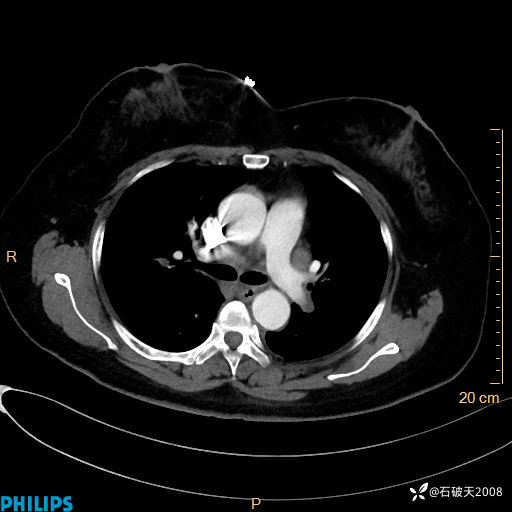

肺结节病?纵膈型肺癌?淋巴瘤?有点意思,欢迎围观

女 52岁 主 诉:咳嗽10余天,咳痰2天。

现病史:10余天前无明显诱因出现咳嗽,呈阵发性干咳,伴咽喉部发痒,无咽痛,无咳痰,无鼻塞、流涕、打喷嚏,无发热、畏寒、寒颤,无头痛、头晕,无胸闷、胸痛,无反酸、烧心,无腹痛、腹泻,无尿频、尿急,无皮疹等,在当地诊所求治,给予口服药物治疗(具体不详),病情无好转。遂在当地社区卫生服务中心开具口服药物治疗(具体不详),疗效欠佳。2天前出现咳痰,在我院门诊求治,行胸部CT提示肺部感染,建议住院,患者要求口服药物治疗,目前仍咳嗽、咳白色粘痰,白天量多,夜间自觉喉部喘鸣音,遂再次来院就诊,以“肺部感染”为诊断收入院。发病以来,神志清,精神可,饮食可,夜间睡眠差,大小便正常,近期体重无明显变化。

肺窗